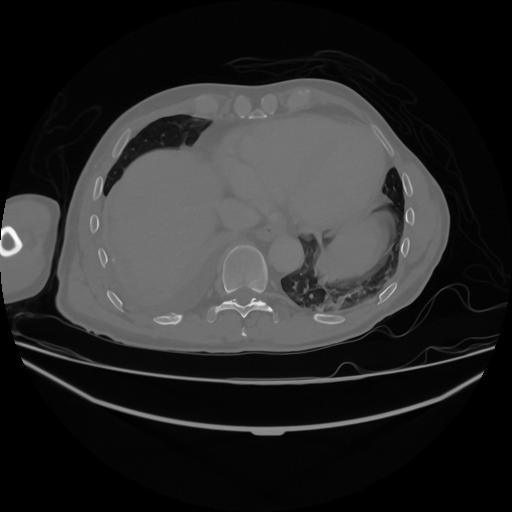

5 CUERPO,CE,Vol,1.0,CUERPO,,